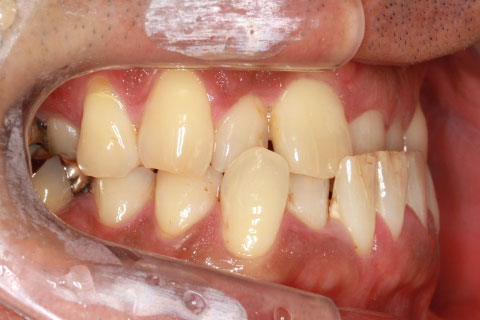

矯正期間24ヶ月

フルリンガル矯正1(上下の歯を舌側矯正で治療)

治療前

治療中

治療後

- 年齢・性別

- 33歳女性

- 治療期間

- 2年0ヶ月

- 抜歯

- 上顎4番抜歯。下顎5番欠損。

- 治療費

- 120万円(税込み)

- 備考

- フルリンガル矯正

- 治療内容

- 上顎前歯の叢生改善および下顎前歯の空隙閉鎖

- 施術の副作用(リスク)

- 装置が裏側について、目視ができないため、しっかりとブラッシングができているかどうかわかりにくい。